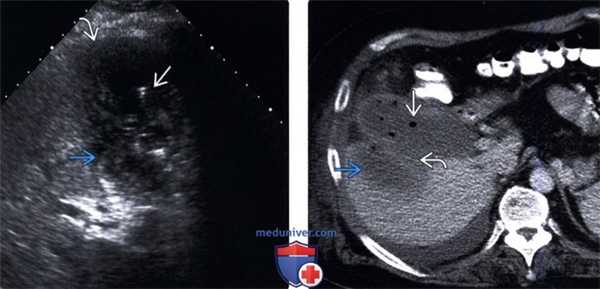

(Левый) На продольном УЗ срезе визуализируется желчный пузырь, содержащий не отбрасывающий тени опухолевидный сладж.

(Правый) Положение пациента на боку. На продольном срезе в просвете желчного пузыря определяются подвижные множественные флотирующие эхо-сигналы. Обратите внимание на почти спавшийся желчный пузырь и выраженное утолщение его стенки.